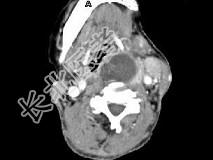

- 单项选择题女,64岁, 发现双甲状腺肿大1个月余,CT如图所示, 最可能的诊断是 ( )

A、结节性甲状腺肿

B、甲状腺腺瘤

C、甲状腺癌并淋巴结转移

D、甲状腺转移瘤

E、甲状腺结核